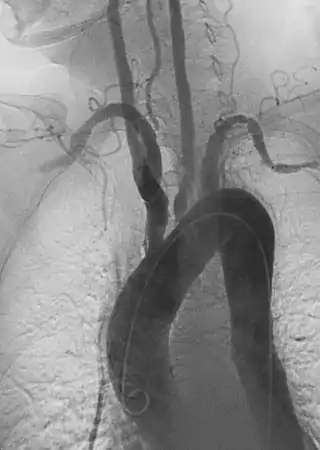

La arteritis de Takayasu también conocida como enfermedad sin pulso, tromboaortopatía oclusiva, síndrome del arco aórtico, es una enfermedad inflamatoria (vasculitis granulomatosa) de causa desconocida que afecta a la aorta y a sus ramificaciones, incluyendo la arteria carótida.[1] Aunque se han encontrado casos en todo el mundo, se muestra con frecuencia en mujeres jóvenes de Asia. Las mujeres con esta enfermedad superan en número a los hombres por 8 a 1, y la edad de comienzo se encuentra entre los 15 y los 30 años. En el mundo occidental, la arteriosclerosis es una causa más frecuente de obstrucción de los vasos sanguíneos.

Alrededor de la mitad de los pacientes desarrollan una enfermedad sistémica inicial con síntomas de malestar, fiebre, hiperhidrosis, pérdida de peso, artralgia y fatiga. Suele haber anemia y elevación en la sedimentación de eritrocitos. A esta fase le sigue otra caracterizada por cambios inflamatorios en la aorta y sus ramificaciones. La mitad de los pacientes con arteritis de Takayasu se presenta sólo con cambios vasculares, sin que le preceda una enfermedad en el sistema. En la última fase, la debilidad arterial puede crecer hasta llegar a un aneurisma.

Cuatro tipos de arteritis han sido descritas:

- Tipo I - Tipo clásico sin pulso que implica la aorta y sus derivaciones.

- Tipo II - Aorta abdominal y sus ramas.

- Tipo III - Suma que implica el tipo I y II.

- Tipo IV - Conlleva a la afección de la arteria pulmonar